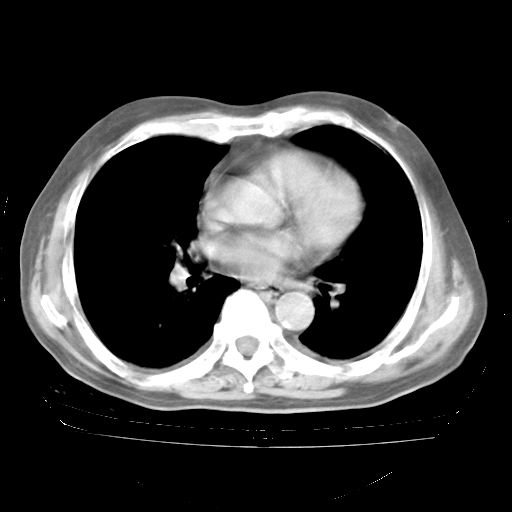

4月28日肺部CT——再次出现类似去年5月9日——透光度降低,“间质性”改变。

4月28日肺部CT